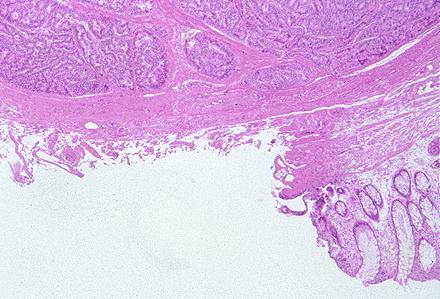

카시노이드종양 (대장)

내시경적 용종절제술로 절제된 직장 카시노이드

카시노이드종양/

대장/직장

마이크로

sm